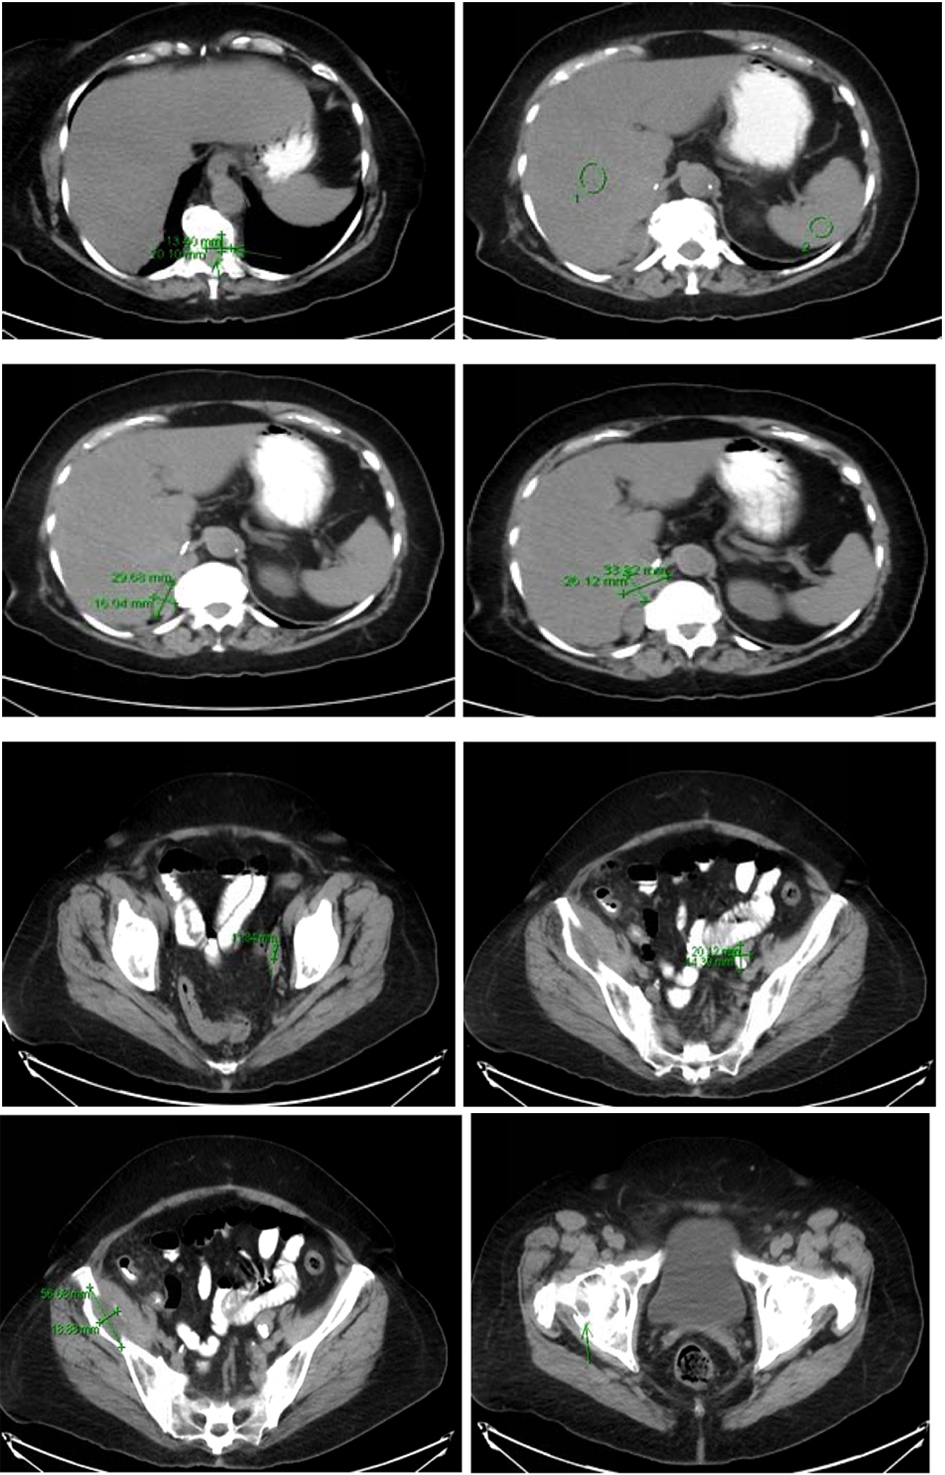

Computer tomography of the abdomen also showed increased soft tissue nodules in the right adrenal bed with multiple lytic osseous lesions, and distal ileal wall thickening secondary to post radiotherapy changes (Fig. 5).

![]() Click for large image | Figure 5. Multiple predominantly osseous metastasis with metastasis in the right iliac bone, increased conspicuity of several soft tissue nodules in the right adrenalectomy bed consistent with recurrent neoplasm, a superior structure measuring 3.4 × 2.6 cm not well defined from adjacent unopacified liver is seen, the right diaphragmatic crus and the unopacified IVC and an adjacent posterior nodule measuring 3 × 1.6 cm is noted. |